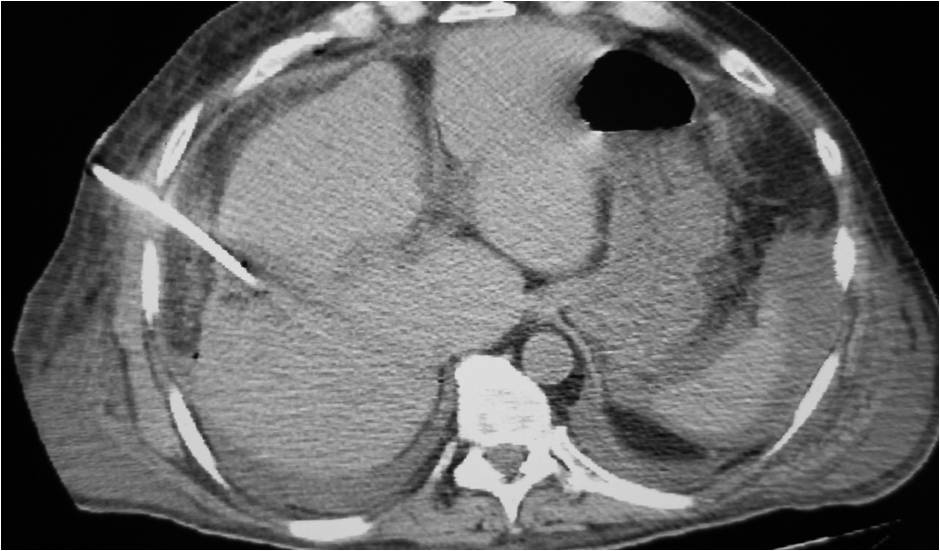

- Large abdominal abscess post- pancreatic surgery

- Successful drainage